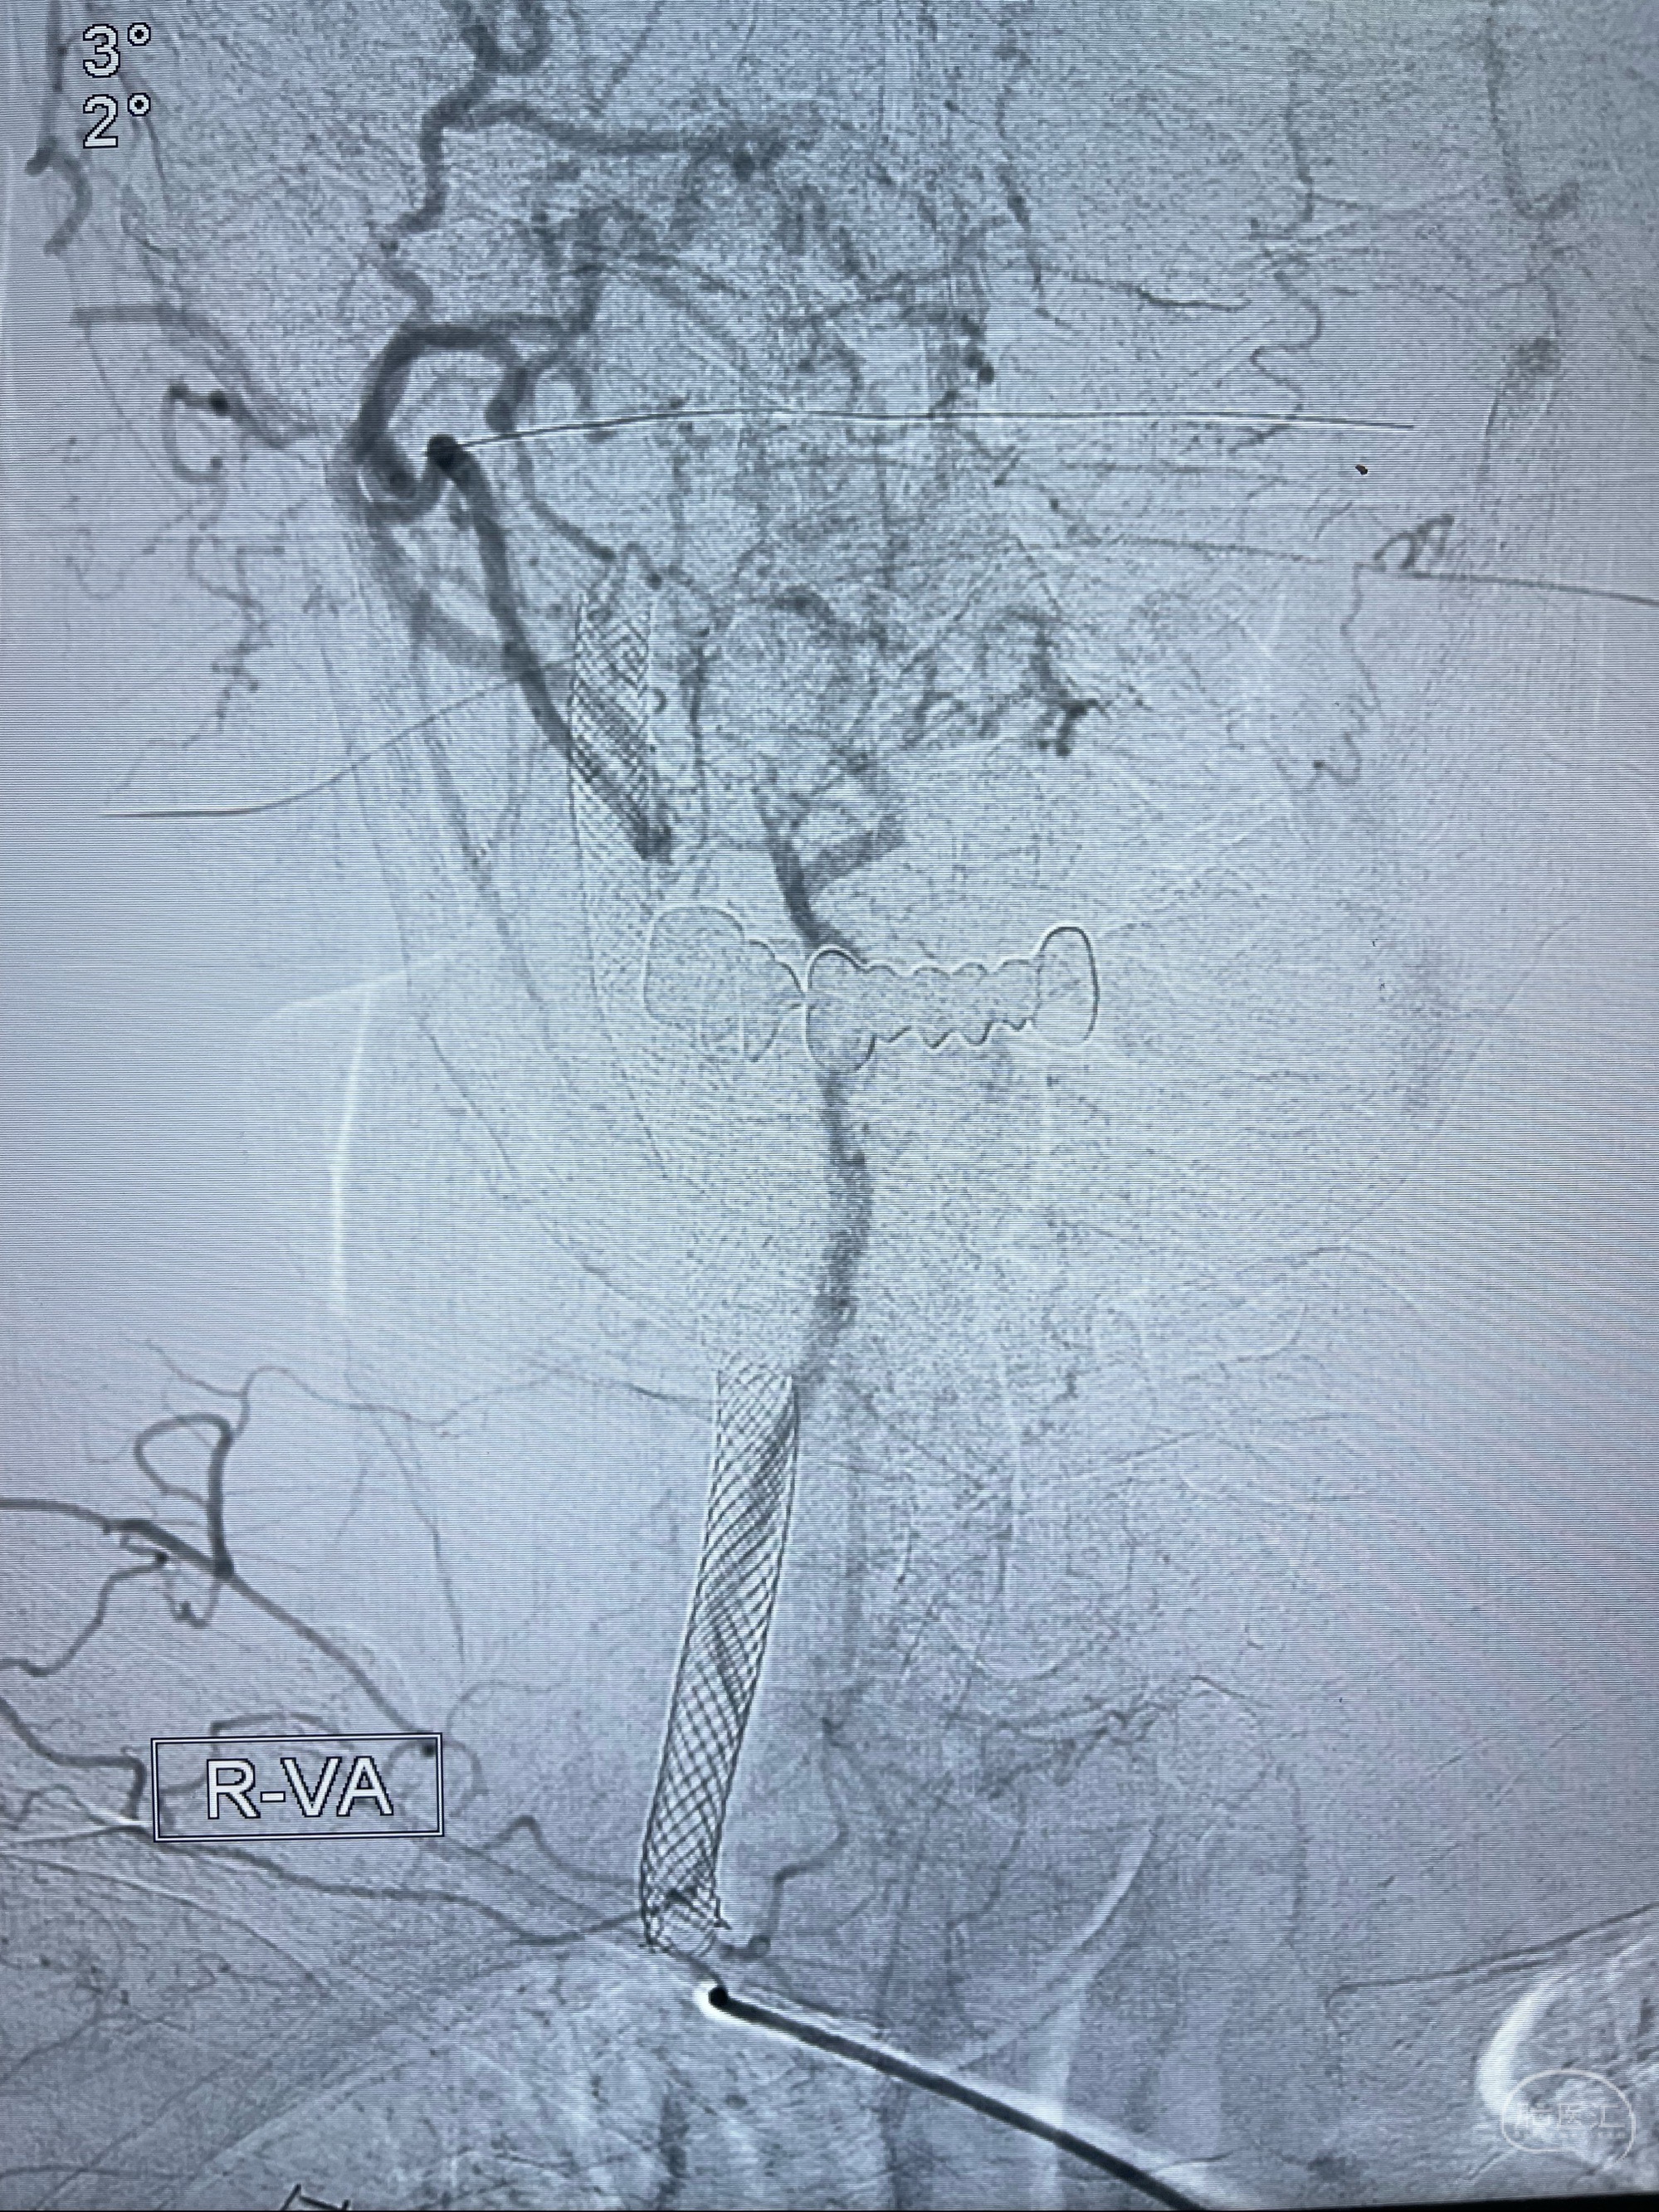

重新行“路径图”,支架导管在微导丝引导下超选择性插入至右侧颈内动脉眼段,4.5-50mmLeo支架释放,远心端位于海绵窦段,近心端位于岩骨段狭窄段以近

即刻造影显示支架贴壁佳

路径图下,5.5-50mmLeo支架导管在微导丝引导下超选择性插入远段Leo支架内

两枚支架部分重叠

多次确认支架位置及打开贴壁情况

支架完全打开,近心端位于原颈动脉支架远心端内